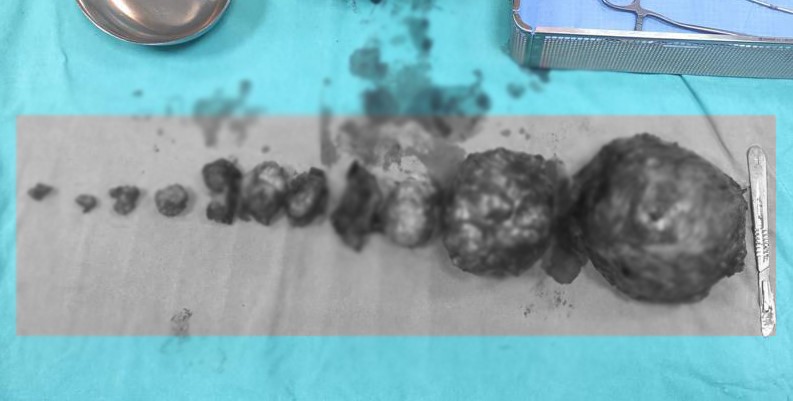

İpekyolu ilçesinde yaşayan Hülya Arvas isimli hamile kadının rahminde çok sayıda miyom tespit edildi. Doktorlar tarafından yapılan ilk muayenede, miyomlar nedeniyle bebeğin düşük riski olduğu ve rahminin de alınabileceği değerlendirildi. Van Eğitim ve Araştırma Hastanesinde düşük tehlikesiyle yatan Arvas, 31 haftalık hamileyken doğum sancıları nedeniyle acil bir şekilde ameliyata alındı. Burada Kadın Hastalıkları ve Doğum Uzmanı Dr. Erhan Hanlıgil ve Op. Dr. Ayşe Yavuz tarafından ameliyata alınan anne, 1 kilo 400 gram ağırlığında bir bebek dünyaya getirdi. Daha sonra doktorlar tarafından kadının rahmi alınmadan yaklaşık 5 kilogram ağırlığında 13 adet miyom da başarılı bir şekilde alındı.

Kadın Hastalıkları ve Doğum Uzmanı Dr. Erhan Hanlıgil ise, hastanın rahminde en büyüğü 20 santimetre olmak üzere 13 adet miyomun çıkarıldığını belirterek, “Miyomların toplam ağırlığı ise 5 kilogramdı. Riskli gebelik olarak takip ettiğimiz hasta kasım ayı içerisinde acil ameliyata aldık ve 13 miyom çıkardık. Bebeğimiz de 1 kilo 400 gram olarak doğmuştu. Bebeği 75 gün boyunca yoğun bakım servisinde takip ettik. Şimdi 6,5 kilogram oldu ve ziyaretimize geldi. Hastamızın kontrollerine baktık, rahminde herhangi bir sorun yok. Kendisi 2-3 yıl sonra tekrar gebelik planlayabilir. Bu sürede gerekli takiplerini yapacağız. Hem hastamız hem de bizler çok mutluyuz” diye konuştu.